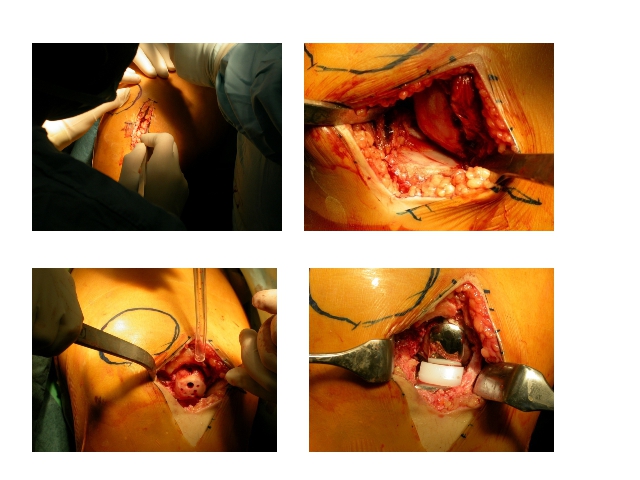

Hip and Knee ProsthesisDec 30, 2021 | Case ExamplesKnee Prosthesis Revisions Total Knee Prosthesis Unikondiler